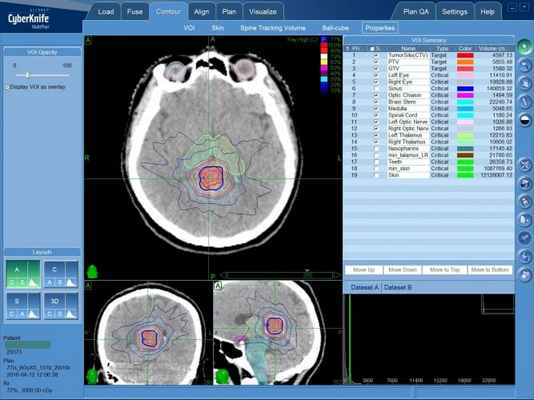

Опухоль шишковидной железы: план лечения на системе КиберНож

(а) МРТ, Т1-ВИ, сагиттальный срез: у мужчины 21 года с жалобами на головную боль определяется объемное образование, расположенное в пинеальной области, в сочетании с обструктивной гидроцефалией, расширением III желудочка и опущением миндалин мозжечка. Дифференциальный диагноз при диагностической визуализации должен проводиться между опухолью паренхимы эпифиза промежуточной дифференцировки (ОПЭПД), пинеобластомой и герминомой.

(б) МРТ, Т2-ВИ, аксиальный срез: определяется очень крупная опухоль паренхимы эпифиза промежуточной дифференцировки (ОПЭПД), распространяющееся в желудочковую систему. Обратите внимание на неоднородный на Т2-ВИ сигнал от объемного образования, в структуре которого отмечаются множественные кистозные очаги, что характерно для опухоли паренхимы эпифиза промежуточной дифференцировки (ОПЭПД).